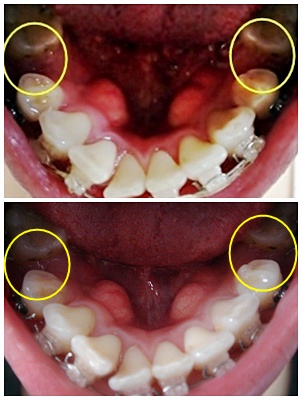

└▷ 므흣~ 아래 앞니에 브라켓 새로 붙인 거 보이시나요~!? ^^ 설마 또 저만 보이는 거임..? ㅠㅠ

└▷ 짜잔~ 이렇게 비교해서 보면 똭~! 보이죠? ㅋㅋ 빨간 동그라미가 붙어 있는 새 브라켓임.. +ㅁ+)b

└▷ 이번 진료는 3주만에 간 거라.. 발치공간이 많이 안 줄었을 거라 생각했는데~

사진찍어서 보니 발치공간이 또 줄었네요 ㅋㅋ (유후~ 기특한 치아들~ 잘 움직이고 있구나~!)